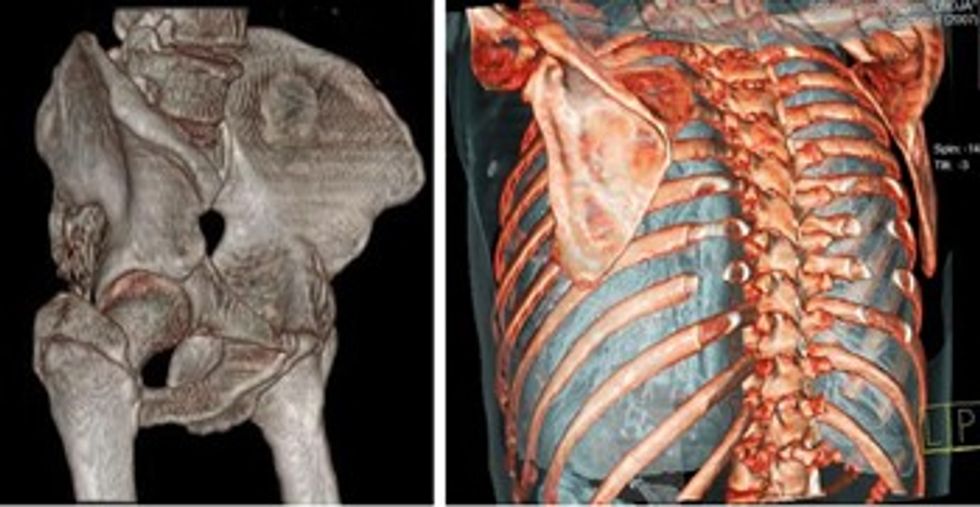

Me 3D mundësohet vizualizimi i kockave dhe e kurrizit me tomografi të kompjuterizuar në tre rrafshe dhe me vizualizim të sipërfaqes së kockës e cila mund të analizohet në të gjashtë anët e saja.